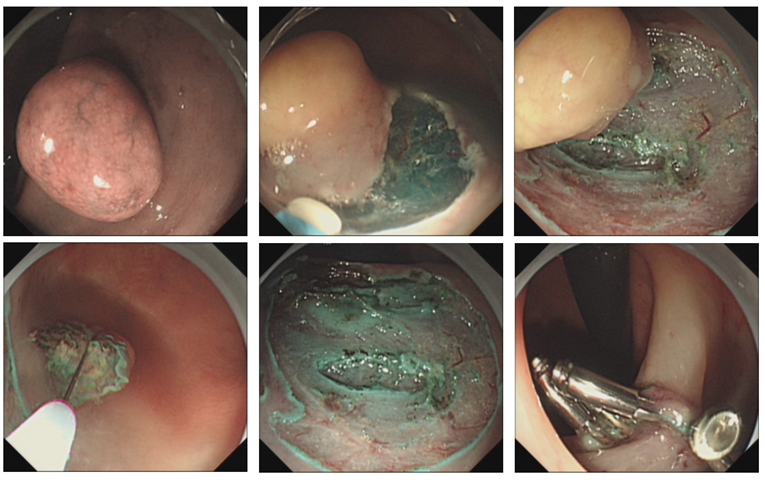

结合患者肠镜及超声内镜检查,诊断考虑直肠SMT:神经内分泌肿瘤,可考虑行内镜下治疗。手术过程如图:内镜头端置透明帽,在病变周围黏膜下注射甘油果糖+肾上腺素+亚加蓝,病变抬举可,一次性高频切开刀沿病变外缘约1~2 mm预切开并逐步剥离,病变来源于黏膜下层,逐步剥离剩余少许边缘组织后,再圈套器高频电凝电切完整切除病变。术中出血点予以一次性热活检钳+APC烧灼处理,安杰思夹子装置7枚封闭创面。

该患者为直肠黏膜下隆起肿物,结合超声内镜检查,诊断考虑直肠神经内分泌肿瘤可能性大,按照20年版的神经内分泌肿瘤诊治专家共识,考虑该直肠黏膜下肿物,大小在2 cm以内,可行内镜下切除治疗。由于病变靠近肛门,我们更换为胃镜操作,同时头端置透明帽协助病变暴露及黏膜下注射。本例患者我们采用了环周预切开内镜黏膜切除术(endoscopic mucosal resection with precutting,EMR-P)。注射后病灶抬举满意,在肿瘤旁正常黏膜处环形切开,然后,在切开槽处放置圈套器予以切除,这样处理可以防止收紧圈套器时肿物的滑动,保证了黏膜和黏膜下组织切割的深度,避免了切缘阳性情况的发生。EMR-P是在单纯的内镜黏膜切除术(endoscopic mucosal resection,EMR)手术基础上进行了改良,相比较于传统EMR来说,完整切除率更高。内镜黏膜下剥离术(endoscopic submucosal dissection,ESD)的所有步骤均在直视下完成,以至于其术后标本更加完整,但相对操作时间及难度都有增加。EMR-P对于直径较小的肿瘤而言,其完整切除率与ESD相比差别不大,但操作时间及手术难度却大大降低。所以EMR-P在直径较小的直肠NET治疗中具备其优势。